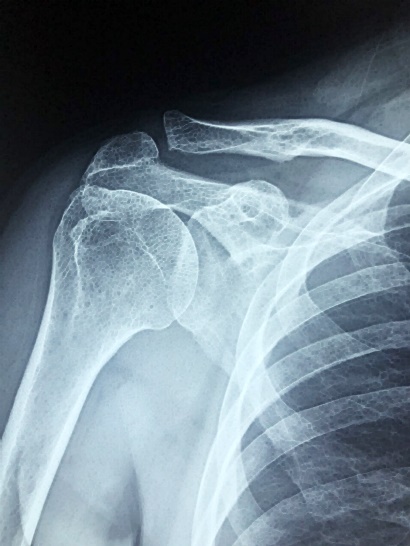

이번에는 어깨 석회화에 대한 이해를 위해 자세히 알아보려고 합니다. 어깨 석회화는 간단히 말해 어깨의 근육에 칼슘이 축적되는 현상을 말하는데요. 이로 인해 어깨에 통증을 느끼거나 움직임에 제약을 느낄 수 있습니다. 오늘 포스팅을 통해, 어깨 석회화가 어떤 것인지, 그 원인은 무엇인지, 그리고 이를 어떻게 관리하고 치료하는지에 대해 상세히 살펴보겠습니다.

어깨 석회화는 바로 어깨 힘줄에 칼슘 결정이 축적되는 현상을 가리키는데요, 이는 어깨를 움직이는 데 필수적인 부위입니다. 그런데 이곳에 칼슘이 쌓이게 되면 통증을 유발하고 움직임에 제약을 가져옵니다.

어깨 석회화의 가장 대표적인 증상은 바로 어깨에서 느껴지는 통증입니다. 석회화의 크기, 위치, 염증 정도에 따라 통증의 정도는 다르게 나타날 수 있습니다. 통증은 주로 어깨 앞부분이나 옆부분에서 느껴지며, 어깨를 드는 동작이나 회전시킬 때 더욱 심하게 느껴질 수 있습니다. 통증은 밤에도 계속 느껴질 수 있어, 수면을 방해하게 될 수도 있습니다. 어깨 석회화의 추가적인 증상으로는 부분적인 부어 있음, 열을 느끼는 증상, 피부가 붉어짐, 그리고 움직임에 제한이 생기는 등이 있습니다.